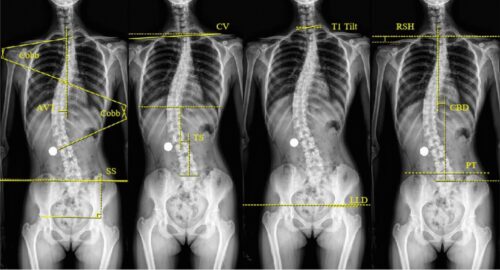

ما هي زاوية كوب؟

زاوية كوب هي الأداة الطبية الأكثر اعتمادًا لقياس شدة انحناء العمود الفقري. ابتكرها الجرّاح الأمريكي جون كوب، وتُستخدم لتحديد:

مدى الانحناء الحالي.

تطور الحالة مع الوقت.

نوع العلاج المناسب (تحفظي أو جراحي).

كيف يتم قياس زاوية كوب؟

تصوير الأشعة: يُجرى للمريض وهو واقف أو مستلقٍ.

تحديد الفقرات النهائية: اختيار الفقرة الأكثر ميلًا في أعلى وأسفل الانحناء.

رسم الخطوط: رسم خطين على الفقرات المائلة ثم قياس الزاوية الناتجة.

يتميز هذا القياس بالدقة، لكنه قد يتأثر ببعض العوامل مثل: وضعية المريض، اختلاف تقييم الأطباء، ودوران الفقرات.

هل هناك حدود أو عيوب لزاوية كوب؟

رغم أنها الأداة الذهبية للتشخيص، إلا أن لها بعض القيود:

تعطي صورة ثنائية الأبعاد فقط ولا توضح التشوهات ثلاثية الأبعاد.

نسبة خطأ بسيطة (3–5 درجات).

لا تعكس دائمًا مدى تأثير الانحناء على مظهر الجسم أو الأعراض.

بدائل حديثة لقياس زاوية كوب

تقنية EOS: تصوير منخفض الإشعاع يعرض صورة ثلاثية الأبعاد للعمود الفقري أثناء الوقوف.

الرنين المغناطيسي أو الأشعة المقطعية ثلاثية الأبعاد: تكشف الدوران والانحناء الأمامي والخلفي.

طريقة زاوية دوران الفقرات : بديل واعد بدقة عالية تصل إلى ±3 درجات.

زاوية كوب أداة أساسية في تشخيص ومتابعة اعوجاج العمود الفقري، إذ تساعد على تحديد شدة الانحناء وخطة العلاج المناسبة. ورغم وجود بدائل حديثة أكثر دقة، تبقى زاوية كوب المعيار الطبي المعتمد عالميًا.